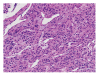

Paragangliomas are extra-adrenal tumors of the autonomic nervous system and may be found within the skull base, neck, chest, and abdomen. When presenting within the abdominal cavity, they may arise as a primary retroperitoneal neoplasm and can mimic vascular malformations or other conditions related to specific retroperitoneal organs such as the pancreas, kidneys, or adrenals. Retroperitoneal paragangliomas are mostly benign with good prognosis; however, they can present with abdominal pain, palpable mass, or hypertensive episodes. Patients should be initially evaluated with catecholamine levels, followed by computed tomography or magnetic resonance imaging to locate the primary lesion. Surgical excision remains the mainstay of treatment, although advanced disease and proximity to vital organs can make excision difficult or impossible. This case report describes a patient who initially underwent work up for a suspected pancreatic head mass which was discovered to be a retroperitoneal paraganglioma by frozen section.